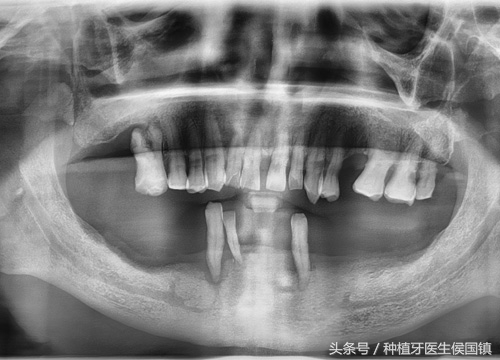

第二步则是初诊了,医生与患者交流,了解患者的情况与修复要求,明确种植方案。过程需要做一个详细的检查,包括测血压、血常规检查、拍牙片检查等等。

牙片